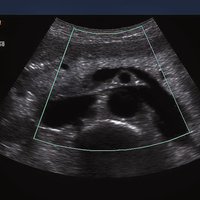

Siemens ACUSON X300 PE Beschreibung

• Abdomen

• Gynäkologie/ Geburtshilfe